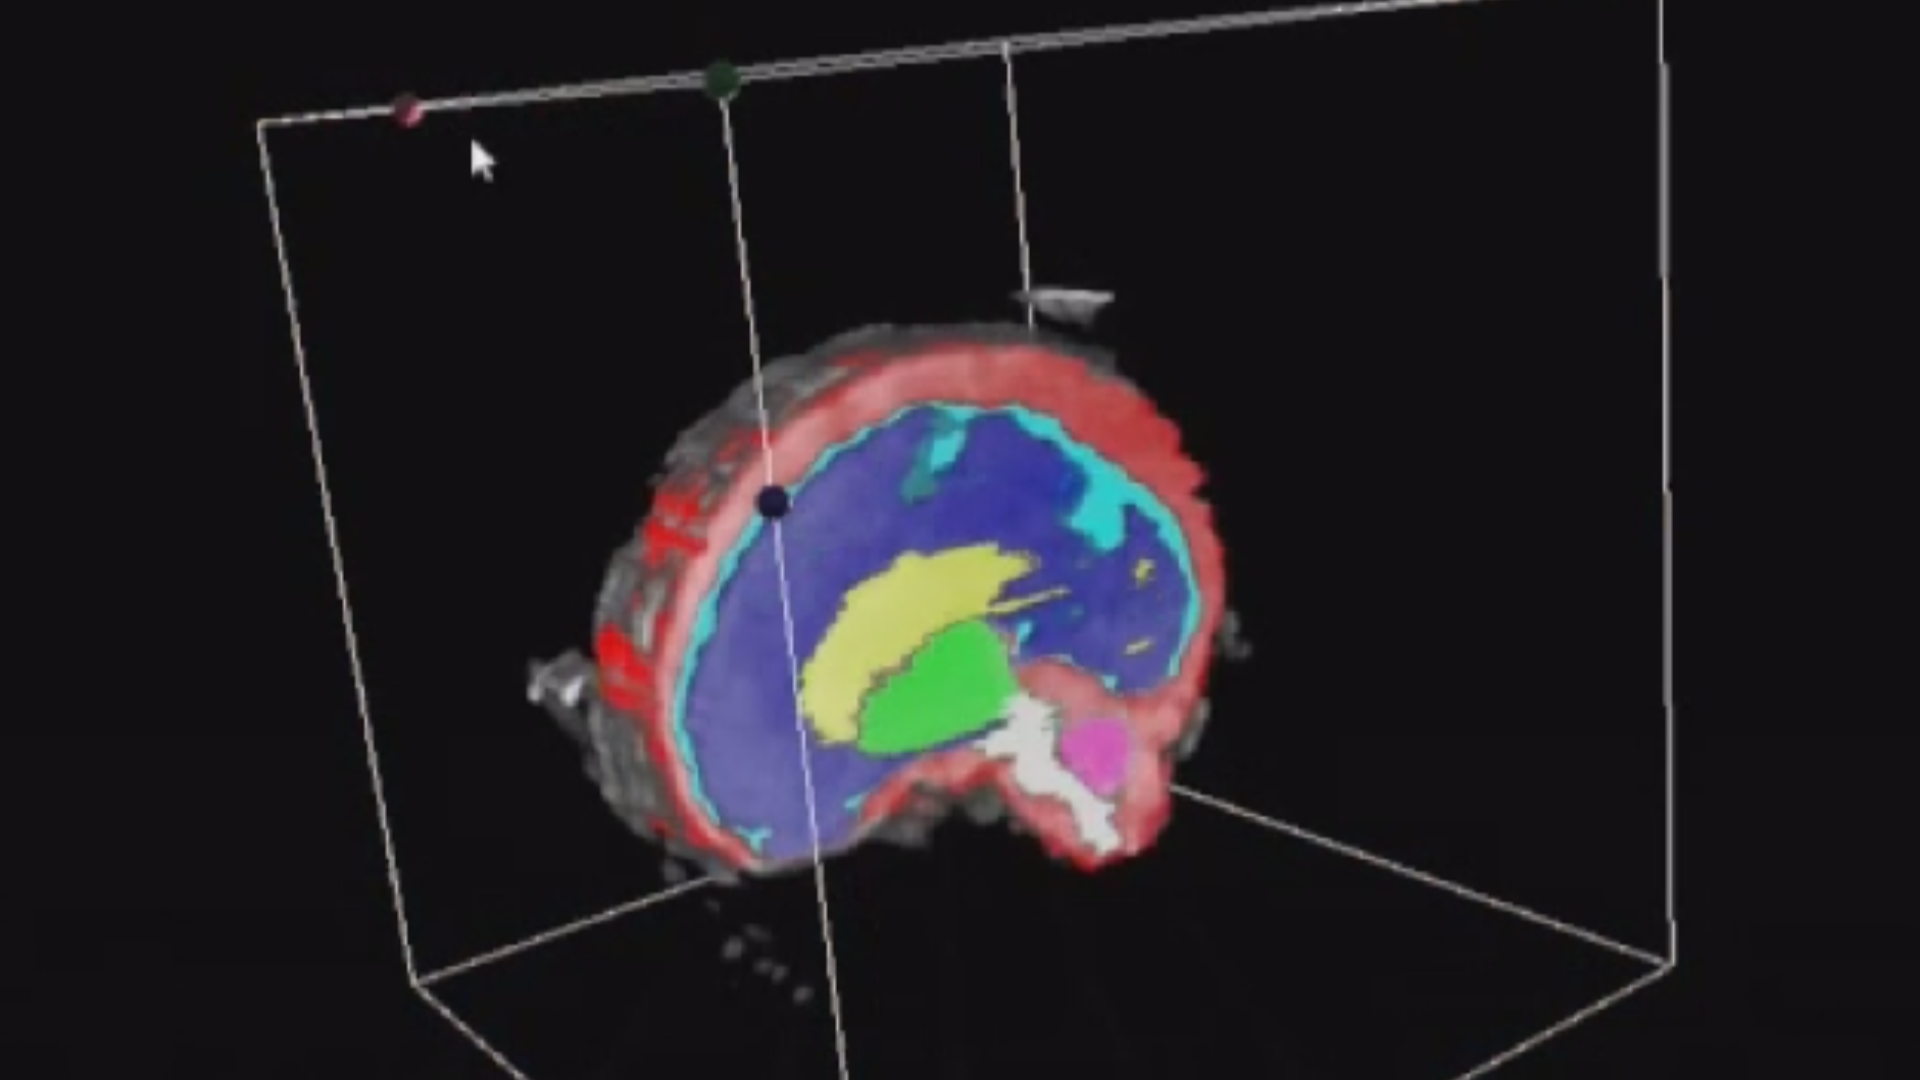

L’Université Paris Cité franchit une nouvelle étape dans le domaine de l’imagerie médicale anténatale avec l’acquisition d’un système d’Imagerie par Résonance Magnétique (IRM) 1,5T ARTIST™ de GE HealthCare. Cet équipement de pointe renforce les capacités de la Plateforme LUMIERE à l’hôpital Necker-Enfants malades, plateforme intégrée de soins, de recherche clinique et d’enseignement en imagerie médicale de la femme enceinte, du fœtus et du placenta.

Implantée à l’hôpital Necker-Enfants malades, la Plateforme LUMIERE est une plateforme unique au monde, qui a vu le jour grâce notamment au soutien de l’Université Paris Cité, de l’AP-HP et de la Fondation LUMIERE.

L’inclusion de ces patientes, depuis leur accueil jusqu’à la réalisation des examens d’imagerie, puis l’analyse des images et l’interprétation des résultats par des équipes expertes, enrichit une base de données structurée, unique au monde, au service de la recherche et de l’innovation en imagerie anténatale et en médecine fœtale.